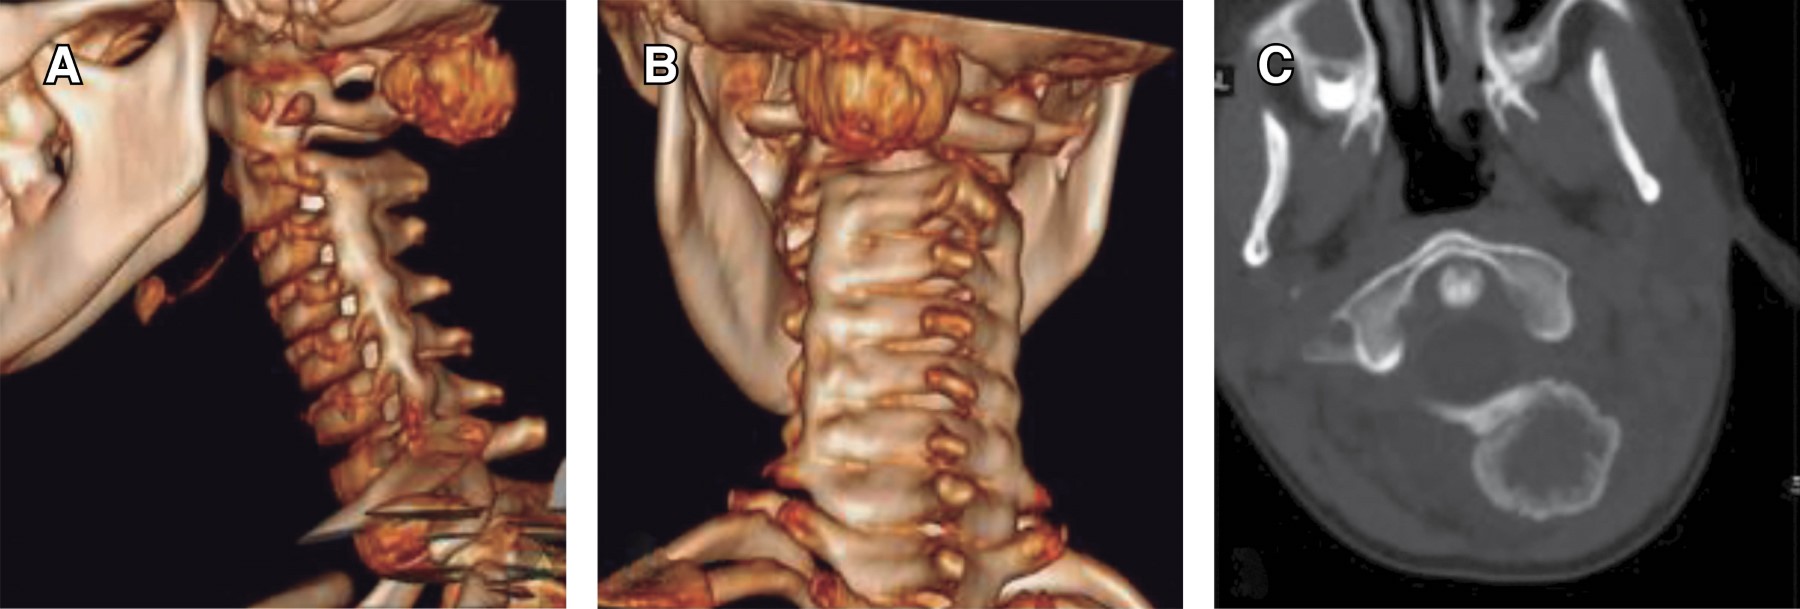

Introduction: myositis ossificans (MO) is described as a non-neoplasic heterotopic bone formation at soft tissues and muscle. It is a rare entity in children, but it must be included within the differential diagnosis of a malignant tumor or an infection. Material and methods: the objective of this retrospective study is to describe three clinical cases of circumscribed myositis ossificans; the first one is a 10-year-old girl with a post-traumatic cervical injury, the second one is an 11-year-old boy with an atraumatic-type distal thigh injury, and the third one is an 8-year-old boy with a post-traumatic right thigh tumor. Results: the diagnosis was made on the basis of the clinical presentation, radiologic imaging and histopathological findings. The results obtained by conservative treatment were good in all cases, with resolution of pain and progressive reduction in size of lesions, without registering complications during follow-up. Conclusion: myositis ossificans is a rare entity, whose diagnosis is usually complex and may require a multidisciplinary team, and whose prognosis is nevertheless favorable.

Figure 1

Figure 2

Figure 3

Figure 4